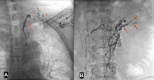

Purpose: Chyluria is a rare condition primarily prevalent in developing countries in tropical regions. In chyluria, there exists the communication between lymphatic vessels and the urinary tract, but the specific mechanism of this communication remains undocumented. The objective of this study was to assess the morphology of the main lymphatic vessels including the uro-lymphatic fistula, the thoracic duct using Magnetic Resonance Lymphangiography (MRL) and Intranodal Lymphangiography (IL).

Materials and methods: A retrospective study spanning five years, from January 2020 to January 2024, included 43 patients diagnosed with chyluria through cystoscopy and quantitative urine testing for triglycerides. These patients underwent MRL and then IL for uro-lymphatic fistula embolization.

Results: The study involved 43 patients with an average age of 66.1 ± 19.5 years, with a male-to-female ratio of 1:2. Uro-lymphatic fistula occurred predominantly in the left kidney (72.1%), followed by the right kidney (20.9%), and both sides (7%). MRL imaging showed the thoracic duct in 100% of cases but visualized only 84.5% of the uro-lymphatic fistulas. In contrast, IL imaging showed the thoracic duct in 51.5% of patients but visualized uro-lymphatic fistulas in 100% of cases. In the procedure of IL, the average visualization time of the thoracic duct was 45 minutes, with a range of 35 to 69 minutes.

Conclusion: MRL and IL complement each other in diagnosing the main lymphatic vessels in chyluria patients. The observed circulatory stasis in the thoracic duct supports the hypothesis that it contributes to increased pressure in the thoracic duct and the formation uro-lymphatic fistula as collateral circulations.